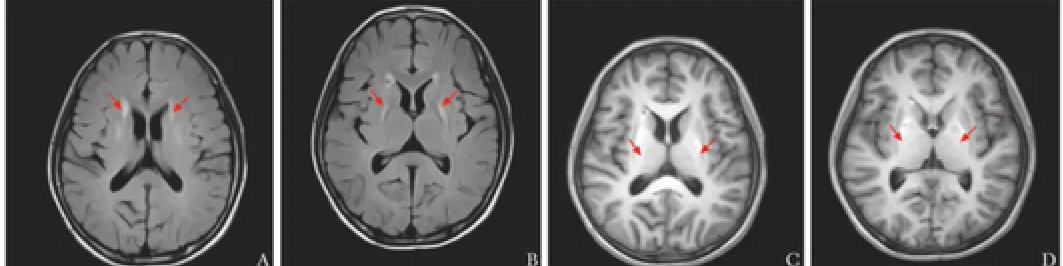

皮肤表现为典型的冻疮样皮疹(A图),少见的有荨麻疹(B图)、雀斑样(C图)、弥漫性银屑病及网状青斑(D图)等。